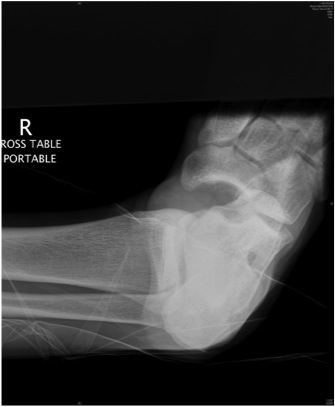

Cuboid Fractures

Types

1. Capsular avulsions

2. Body / Nutcracker fracture

Nutcracker fracture

Epidemiology

- rare

Mechanism

- forced eversion / abduction of forefoot

- cuboid crushed between 4th and 5th MT and calaneum

Pathology

- displaced cuboid fracture with subluxation of tarsus